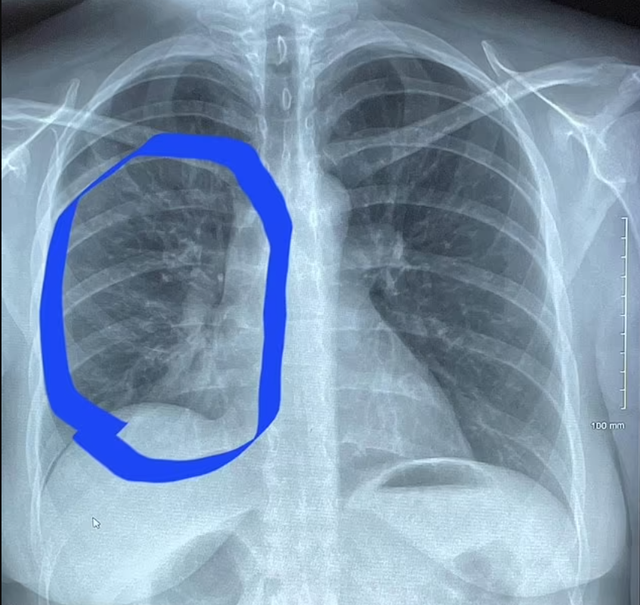

20/05/2024 17:07Cô gái 30 tuổi có phổi trắng bất thường như cụ già 80: Bác sĩ nói 'thủ phạm' là 1 thói quen rất hại

Phổi bị tổn thương nặng nề

Tháng trước, Hannah Roth, 30 tuổi, đến từ Newport, Tennessee, Mỹ, nhận thấy có âm thanh lạ khi cô hít vào. Sau đó, cô bị sốt 40 độ. Hai triệu chứng này khiến cô quyết định đi khám.

Roth đã rất kinh hoàng khi các bác sĩ phát hiện cô bị viêm phổi, nguyên nhân cụ thể là do hút thuốc lá điện tử.

Viêm phổi có thể phát sinh do hít phải các chất có trong tinh dầu trong thuốc lá điện tử, gây ra phản ứng viêm trong phổi.

Roth nói cô đã hút thuốc lá điện tử hằng ngày trong suốt 4 năm qua. Trước đó, cô chưa bao giờ hút thuốc lá truyền thống. Cô bắt đầu sử dụng thuốc lá điện tử do căng thẳng trong đại dịch Covid-19. Rất nhanh sau đó, cô hút thuốc lá điện tử mỗi giờ.

Kết quả chụp scan cho thấy phổi của Roth giống như phổi của một người ở độ tuổi 80 hoặc một bệnh nhân đã hút thuốc hàng chục năm.